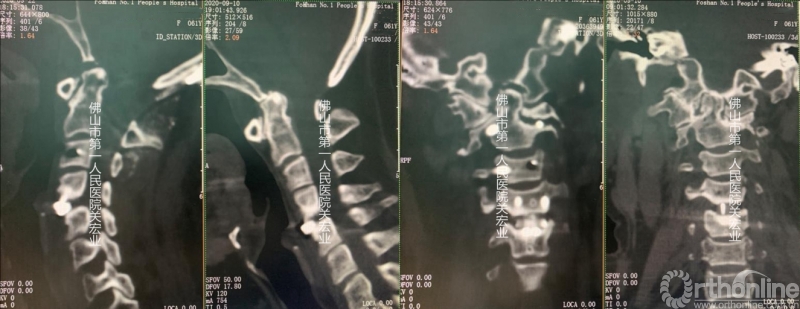

术前CT

影像学术前、术后对比

A:术后颈后、枕部向头顶的放射痛明显缓解。左上肢肌力提高一级,双侧下肢本体感觉改善。术前寰枢椎旋转脱位、下颌偏歪、齿状突上移、脊髓向右侧偏移的情况,术后影像学可见均有明显改善。